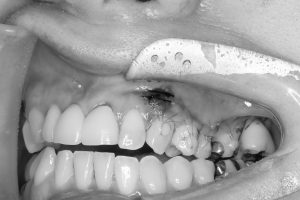

新大久保歯科医院 副院長 猪子です 今日は新しいVISTAキットを用いて根面被覆の処置を行いました。

近年、米国やヨーロッパで臨床応用が進んでいるVISTAテクニックと呼ばれる新しい手法を行う為のキットです。 全層弁が作り易く、多数歯の歯肉退縮にはもってこいのキットです!

しっかり歯肉にゆとりを持たせ、持ち上げる事で、確実な根面被覆を目指します。

あまりにも退縮が進んでいると期待通りの位置までは戻って来ませんが、バイオタイプが改変する事で、歯肉退縮の進行を抑制することが出来ます!

糸がとれるのが待ち遠しいですね